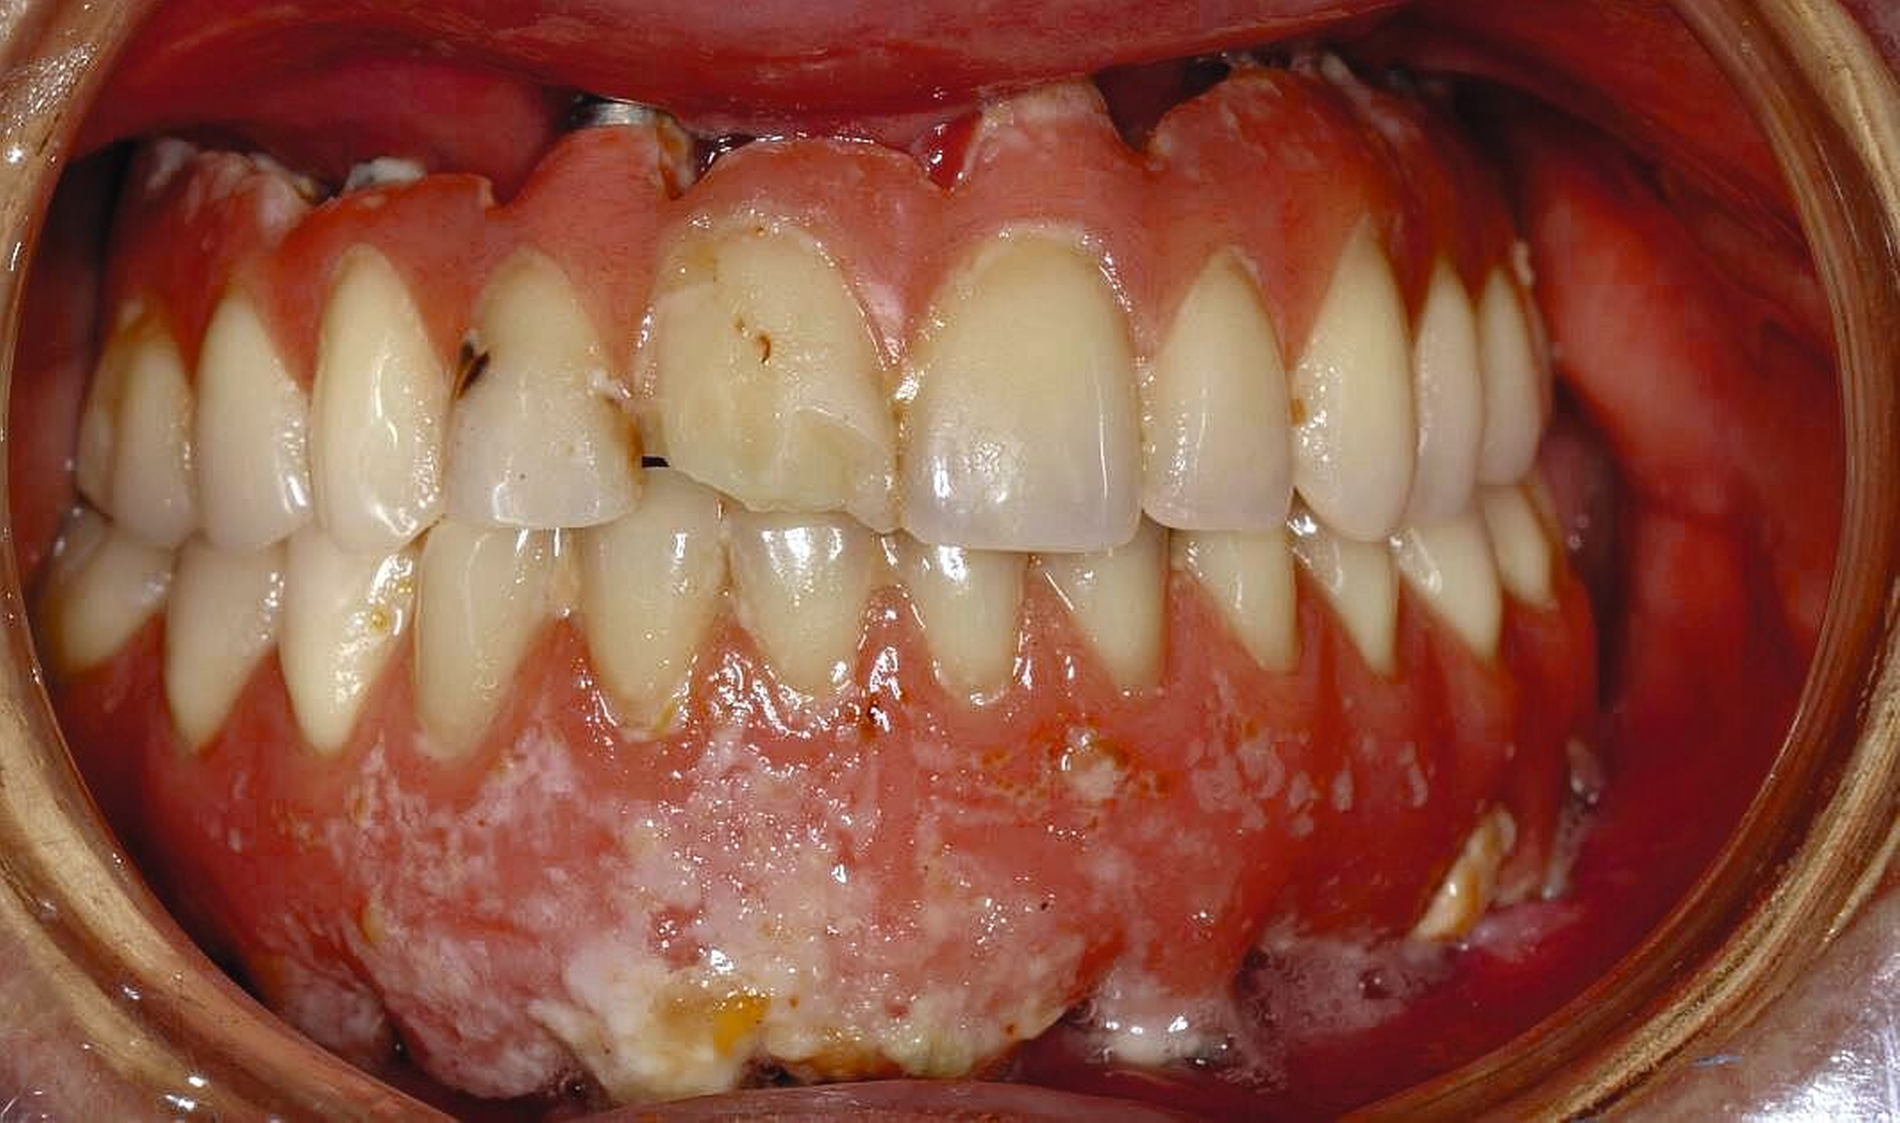

Die Herausforderungen der zahnmedizinischen Betreuung im höheren Lebensalter liegen außerhalb der Mundhöhle und haben nur indirekt etwas mit dem Alter zu tun. Im höheren Lebensalter steigt die Gefahr für Erkrankungen und Funktionseinschränkungen wie Gebrechlichkeit (Frailty), Demenz und Depressionen und/oder internistische sowie muskuloskelettale Erkrankungen. Diese Erkrankungen und Funktionseinschränkungen führen zu einer reduzierten Mundhygienefähigkeit der betroffenen Person. In der Folge kommt es besonders im vorgeschädigten Gebiss zu einer schnellen Progression kariöser oder parodontaler Erkrankungen. In Kombination mit organischen Funktionseinschränkungen wie zum Beispiel einer medikamenteninduzierten Xerostomie führt die Summation der Noxen – auch bei Personen, die ihre Mundgesundheit bis dato aufrechterhalten haben – zu oralen Komplikationen wie Zahnverlust und Entzündungen (Abbildung 1).